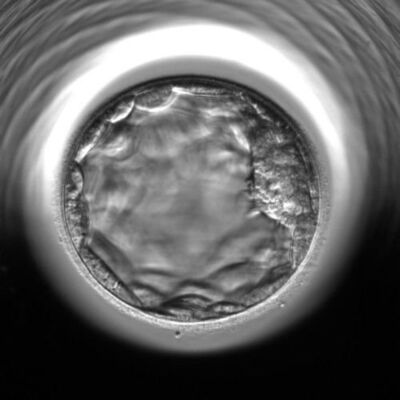

Harvard Üniversitesinde bir Türk profesör tarafından geliştirilen ve Türkiye'de aynı zamanda uygulanmaya başlayan Mikro Akışkan Çip teknolojisiyle adeta samanlıkta iğne arar gibi canlı sperm aranıyor. Prof. Dr. Haşmet Mesut Özsoy, Türk profesörün geliştirdiği bu yöntemin gebelikte başarı oranlarını bir buçuk katına çıkararak tıp dünyasında adeta çığır açıldığını söyledi.

Özel Gözde İzmir Hastanesinde Kadın Hastalıkları ve Doğum Uzmanı Prof. Dr. Haşmet Mesut Özsoy, Harvard Üniversitesinde bir Türk profesör tarafından geliştirilen ve Türkiye'de 2016 yılında uygulanmaya başlayan 'Mikro Akışkan Çip' teknolojisiyle tıp alanında kısırlık (infertilite) tedavilerinde çok önemli gelişme kaydedildiğine dikkat çekti.

Bu yöntemde çok özel tekniklerle canlı sperm arandığını belirten Prof. Dr. Özsoy, "Sağlıklı spermler ve diğerlerine göre daha az sağlıklı olan spermler ayırt ediliyor. Sperm çipleri mikro kanalcıklardan oluşuyor. Mikro kanalların görevi de iyi kalitedeki spermlerin seçilmesini sağlamaktır. Çip bebek yöntemiyle, kaliteli ve kalitesiz spermler iki farklı tarafta toplanır. Bir tarafta sağlıklı ve DNA'sı oldukça düzgün olan kaliteli spermler toplanırken; bir tarafta da diğerlerinden daha sağlıksız olan, DNA'sı hasar görmüş sperm toplanır. Böylece sağlıksız olan spermlerin seçilip, gebelik şansını düşürme riski ortadan kaldırılır. Tedavinin birinci aşaması mikro çip yöntemi ile spermlerin ayrıştırılması ve en kaliteli spermin bulunmasıdır. Eş zamanlı olarak anne adayının da yumurta sayısını artırmak için hormon tedavisi uygulanır. Son aşamada ise sperm rahim içine bırakılarak yumurtanın döllenmesi beklenir" diye açıkladı.

Çip bebek yönteminin, kaliteli spermlerin seçilerek daha başarılı aşılama çalışmalarının ortaya çıkmasını sağladığını belirten Özsoy, sözlerine şöyle devam etti: "Geliştirilmiş sperm çipleriyle, aynı bir süzgeç gibi sağlıklı ve kaliteli olan spermler diğer spermlerden ayırt edilmektedir. Mikro kanalcıklar da bulunan bu sağlıklı spermlerin farklı bir yerde depolanması sağlanıyor. Çipe konulan spermler göç eden kuş sürüsü mantığıyla hareket ederek, DNA'sı en iyi olan spermi öne geçirir."